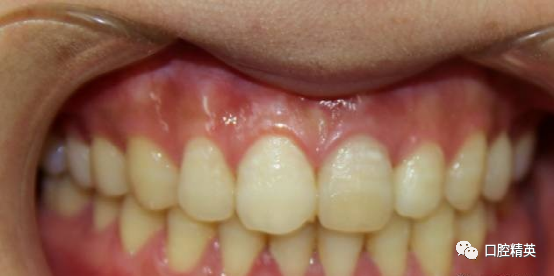

患者,女,31岁。于我院行21根管治疗。21呈生理动度。与邻牙参照略有变色。治疗数周无急性症状,但偶有不适。21唇侧根尖区有膨隆感,扪诊(+),质软,局部牙龈略红肿。转诊时口内照

术前口内照